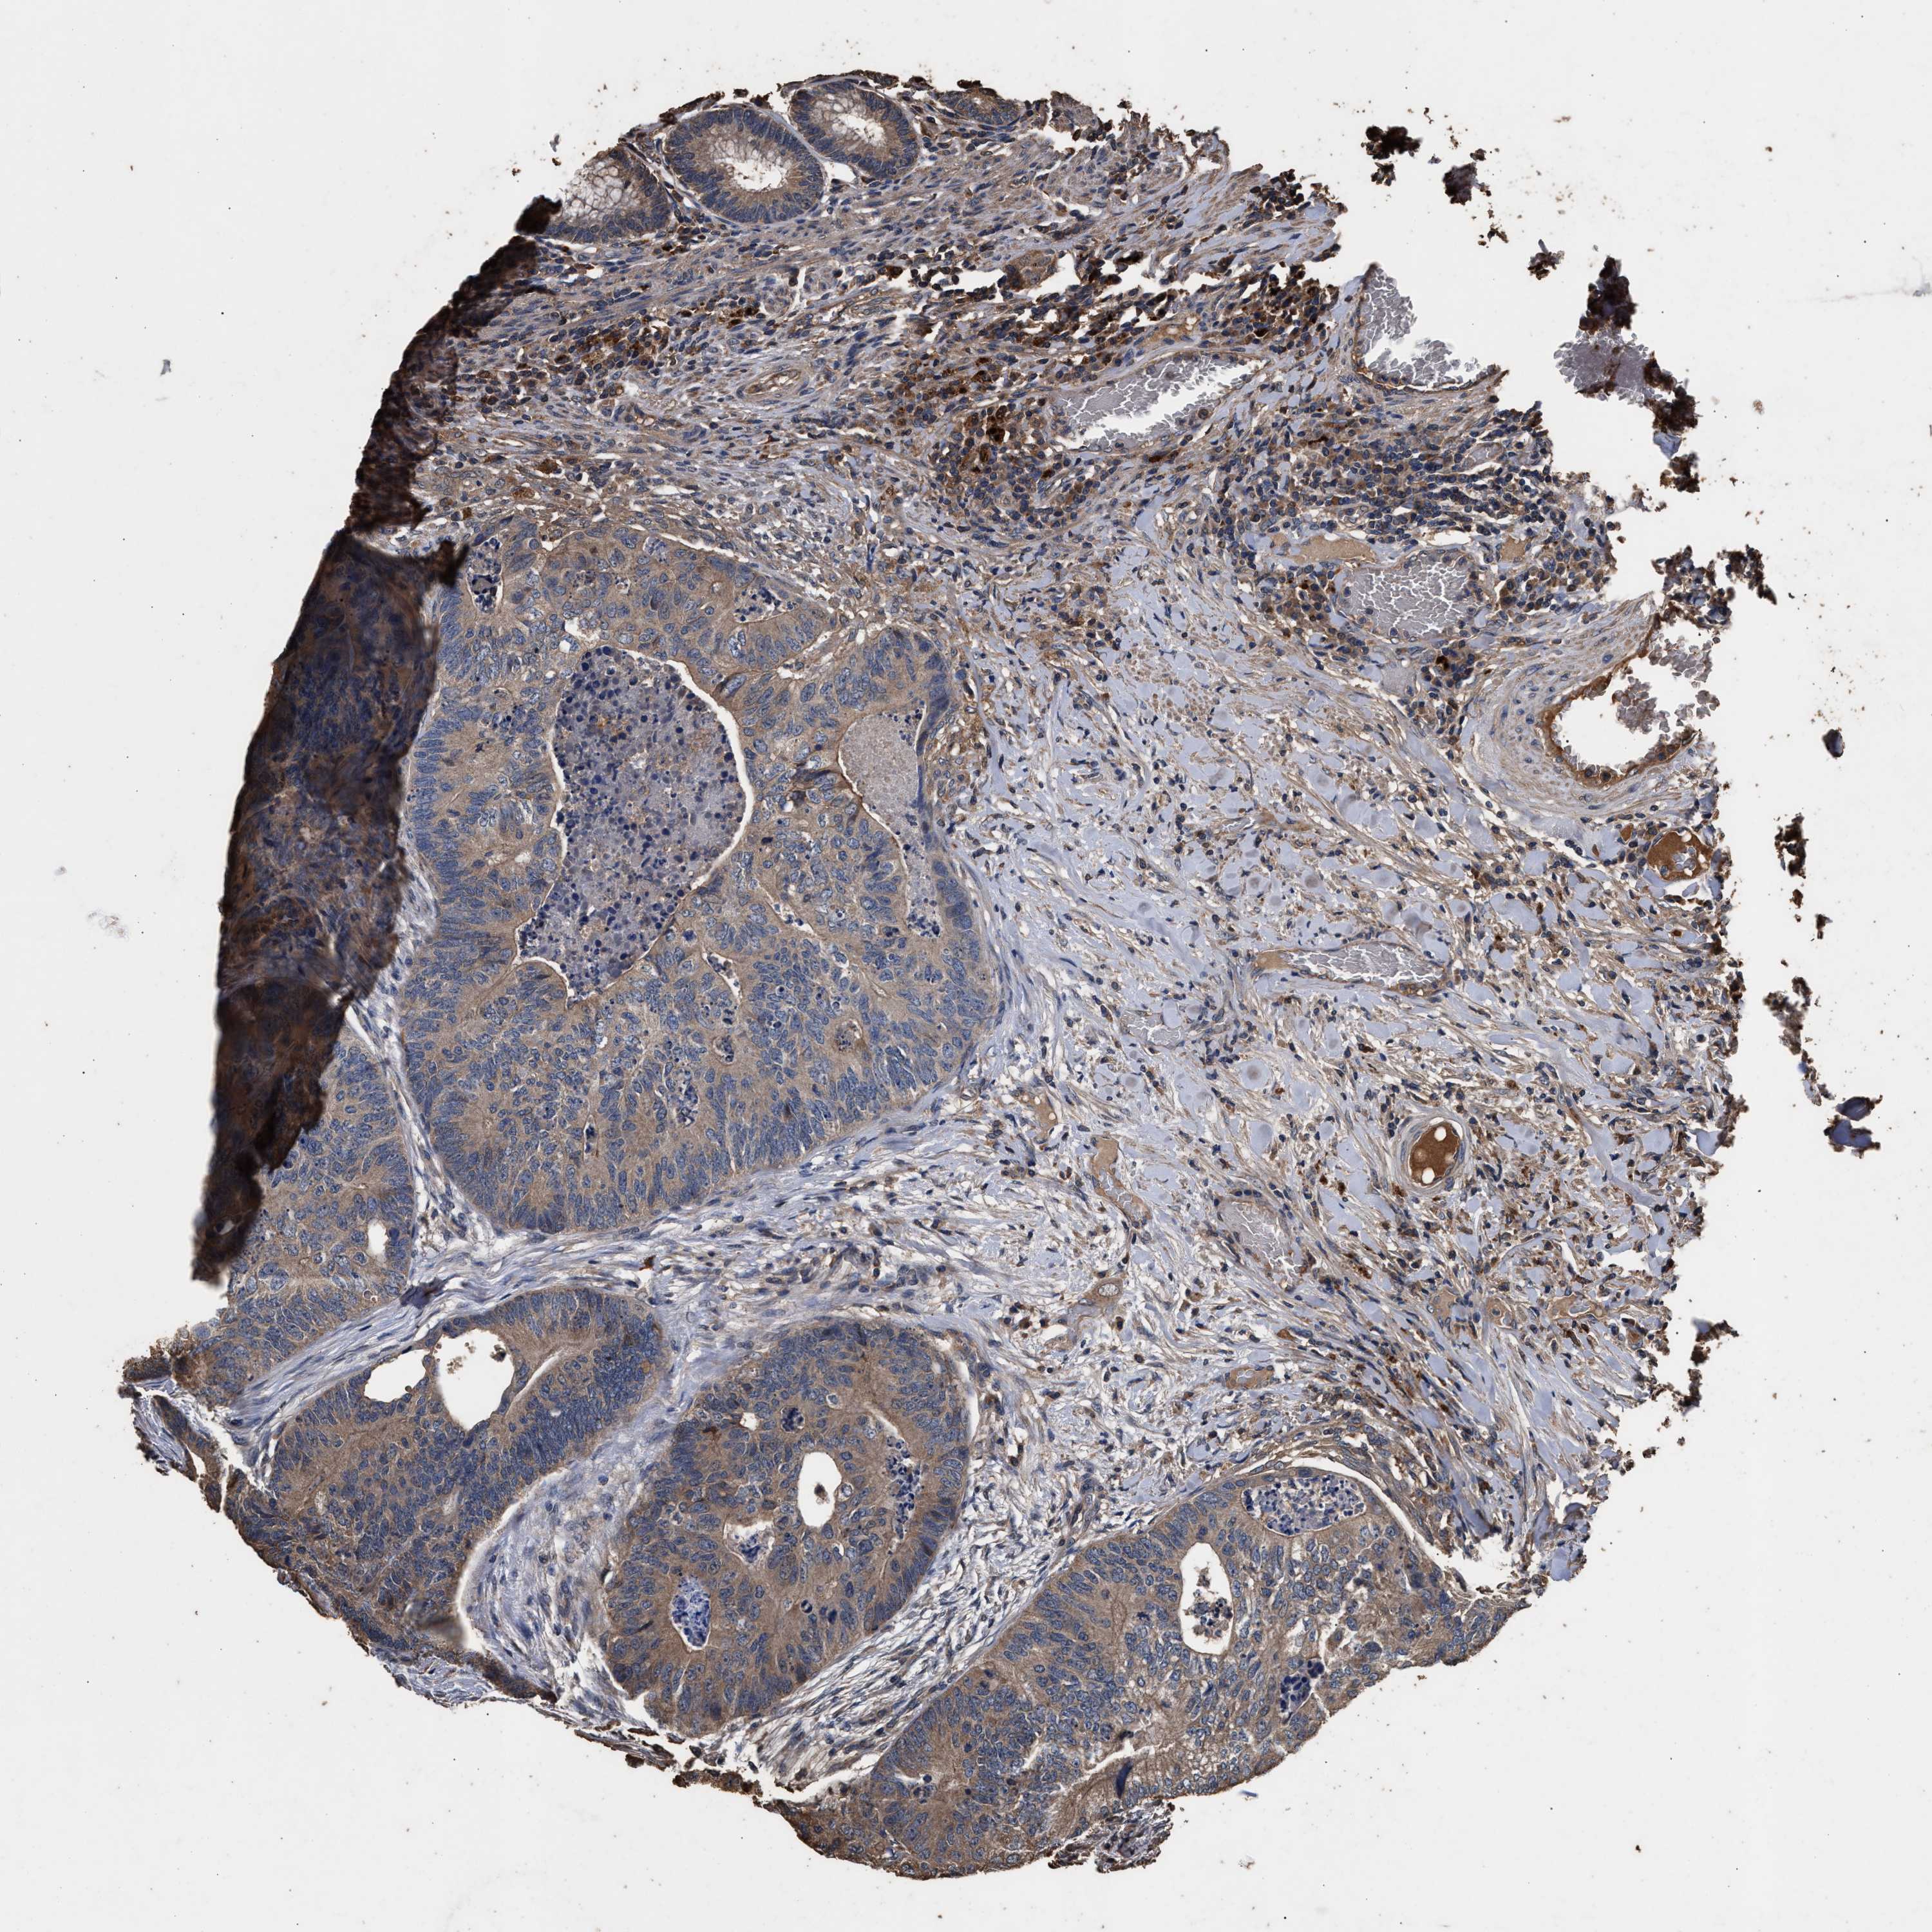

CANCER COLORECTAL CANCER Show tissue menu

Colorectal cancer

Human cancer

Rectum adenocarcinoma